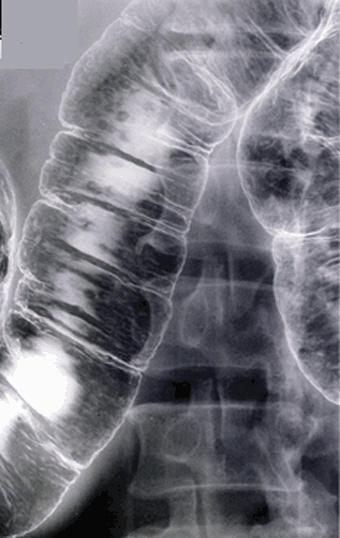

类似炎症性疾患、伴有多样病变的MLP(multiple lymphomatous polyposis)型小肠恶性淋巴瘤

恶性淋巴系统肿瘤/MLP型恶性淋巴瘤

部位(按器官分)

检查方法

多发性肿瘤(同一器官)

有(同时性)

多重性肿瘤(多个器官)